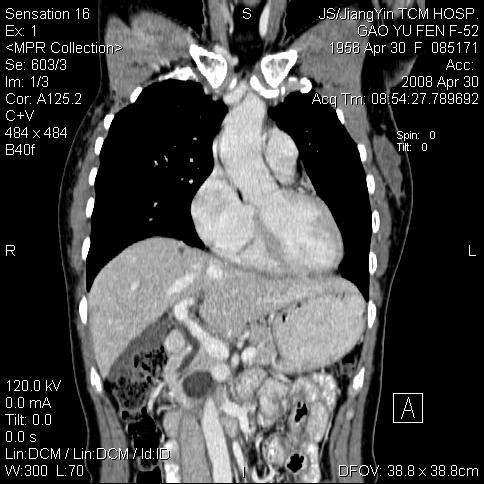

标题: CT13307:肠系膜囊肿? [打印本页]

标题: CT13307:肠系膜囊肿?

囊性淋巴管瘤可能比较大。

良性囊性占位,来源于肠系膜的可能性大

病变位于肾静脉后方,支持腹膜后占位性病变,以囊性淋巴管瘤可能性大.